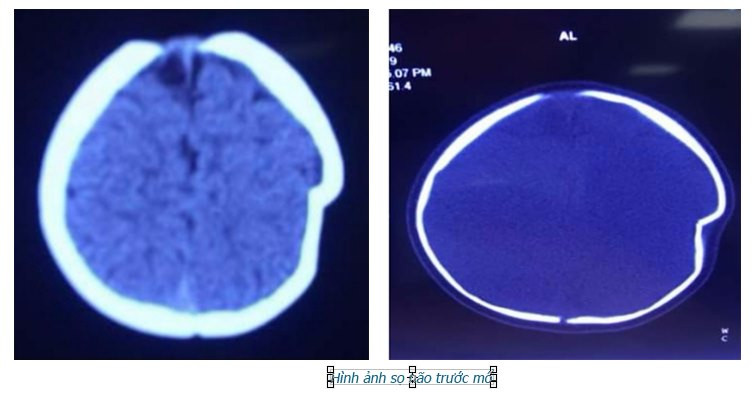

Hình ảnh chụp sọ não của bé L trước khi mổ. Ảnh: Bệnh viện cung cấp

Tại đây, bé L đã được làm các cận lâm sàng và được chẩn đoán lún sọ thái dương đỉnh trái.

Cú va chạm mạnh với mặt đất đã khiến chóp đầu trái của bé bị lún sâu 1cm.